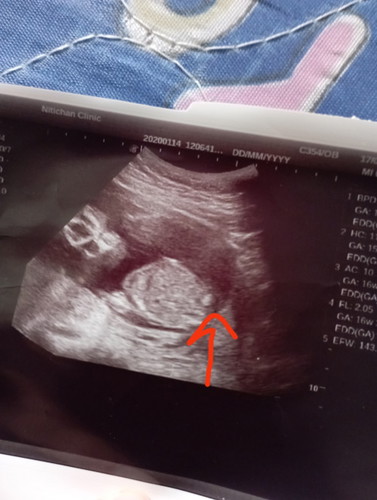

16w+3d เพศน้องยังไม่ชัด

หมอบอกว่าน่าจะเป็น ผช.เพราะน้องมีติ่ง แม่ๆคิดว่าเป็นติ่งเหมือนที่หมอบอกไหมคะ